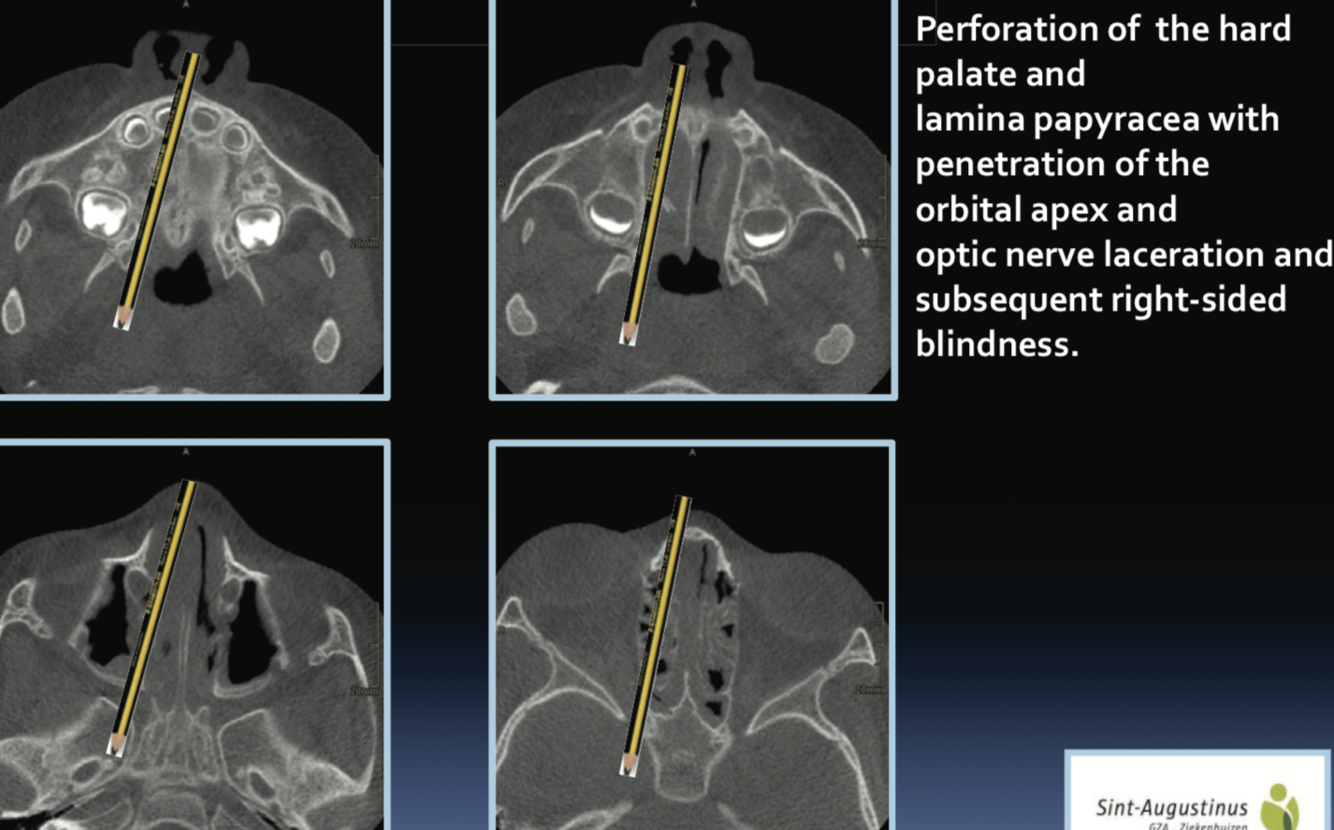

ORBITAL FRACTURES?

Orbital Apex fragments can lead to optic nerve damage

.